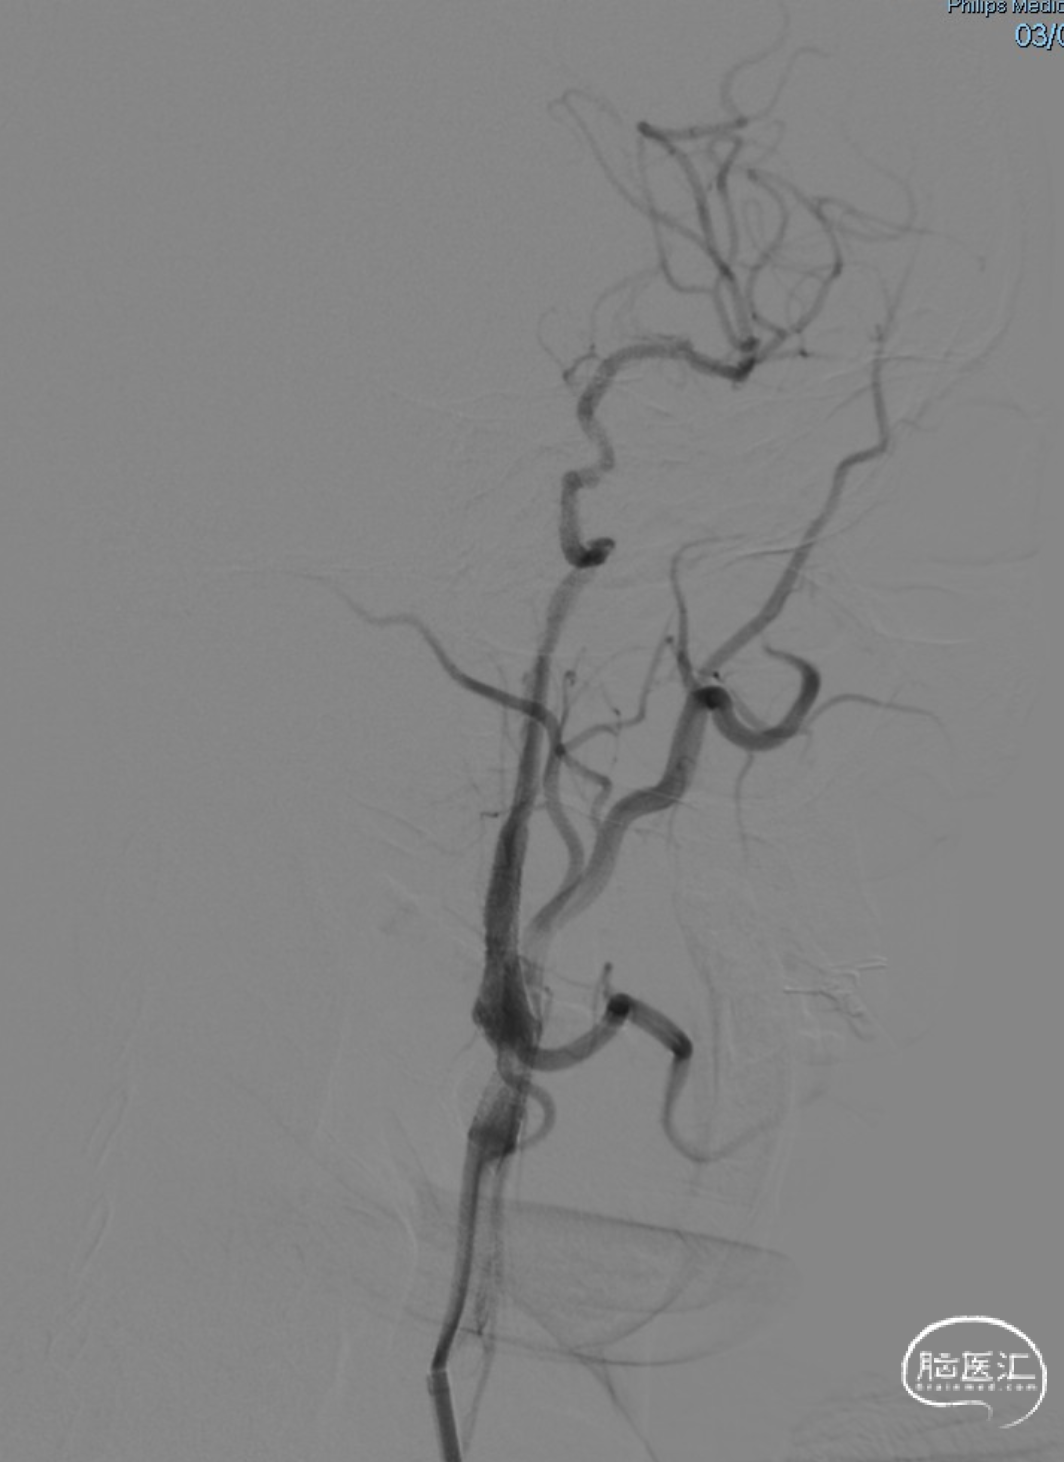

术前DSA造影显示左侧颈内动脉自起始段闭塞,C6眼段以上供血区由颈外动脉眼动脉反向代偿供血,左侧大脑中动脉供血区由前交通动脉代偿供血。

术后即刻影像。

支架植入后造影提示残余狭窄约10%。术中患者生命体征稳定,术后患者恢复良好出院,继续抗血小板聚集及他汀类药物治疗。